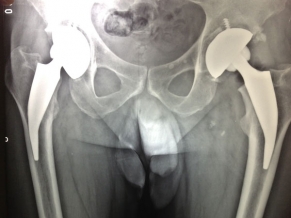

Medicos Argentinos presentan una revolucionaria técnica para tratar la artrosis de cadera

El Dr. Alejandro Druetto, especialista en cirugía de cadera y rodilla, viajó a Dubai para presentar un innovador y efectivo procedimiento para quienes padecen esa dolencia. “Somos el único grupo médico de...